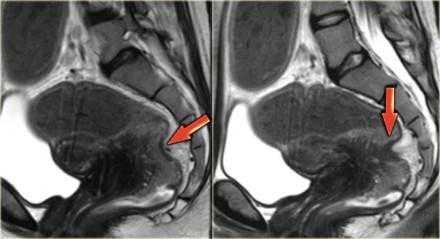

Эндометриоз на МРТ малого таза. В случае циркулярного поражения эндометриоидная инфильтрация может приводить к сужению просвета кишечника. У пациенток при этом возможно изменение формы каловых масс (они становятся узкими в виде «карандаша») либо запоры. На Т2 взвешенных сагиттальных МР-томограммах определяется стеноз прямой кишки на ограниченном участке вследствие циркулярной инфильтрации